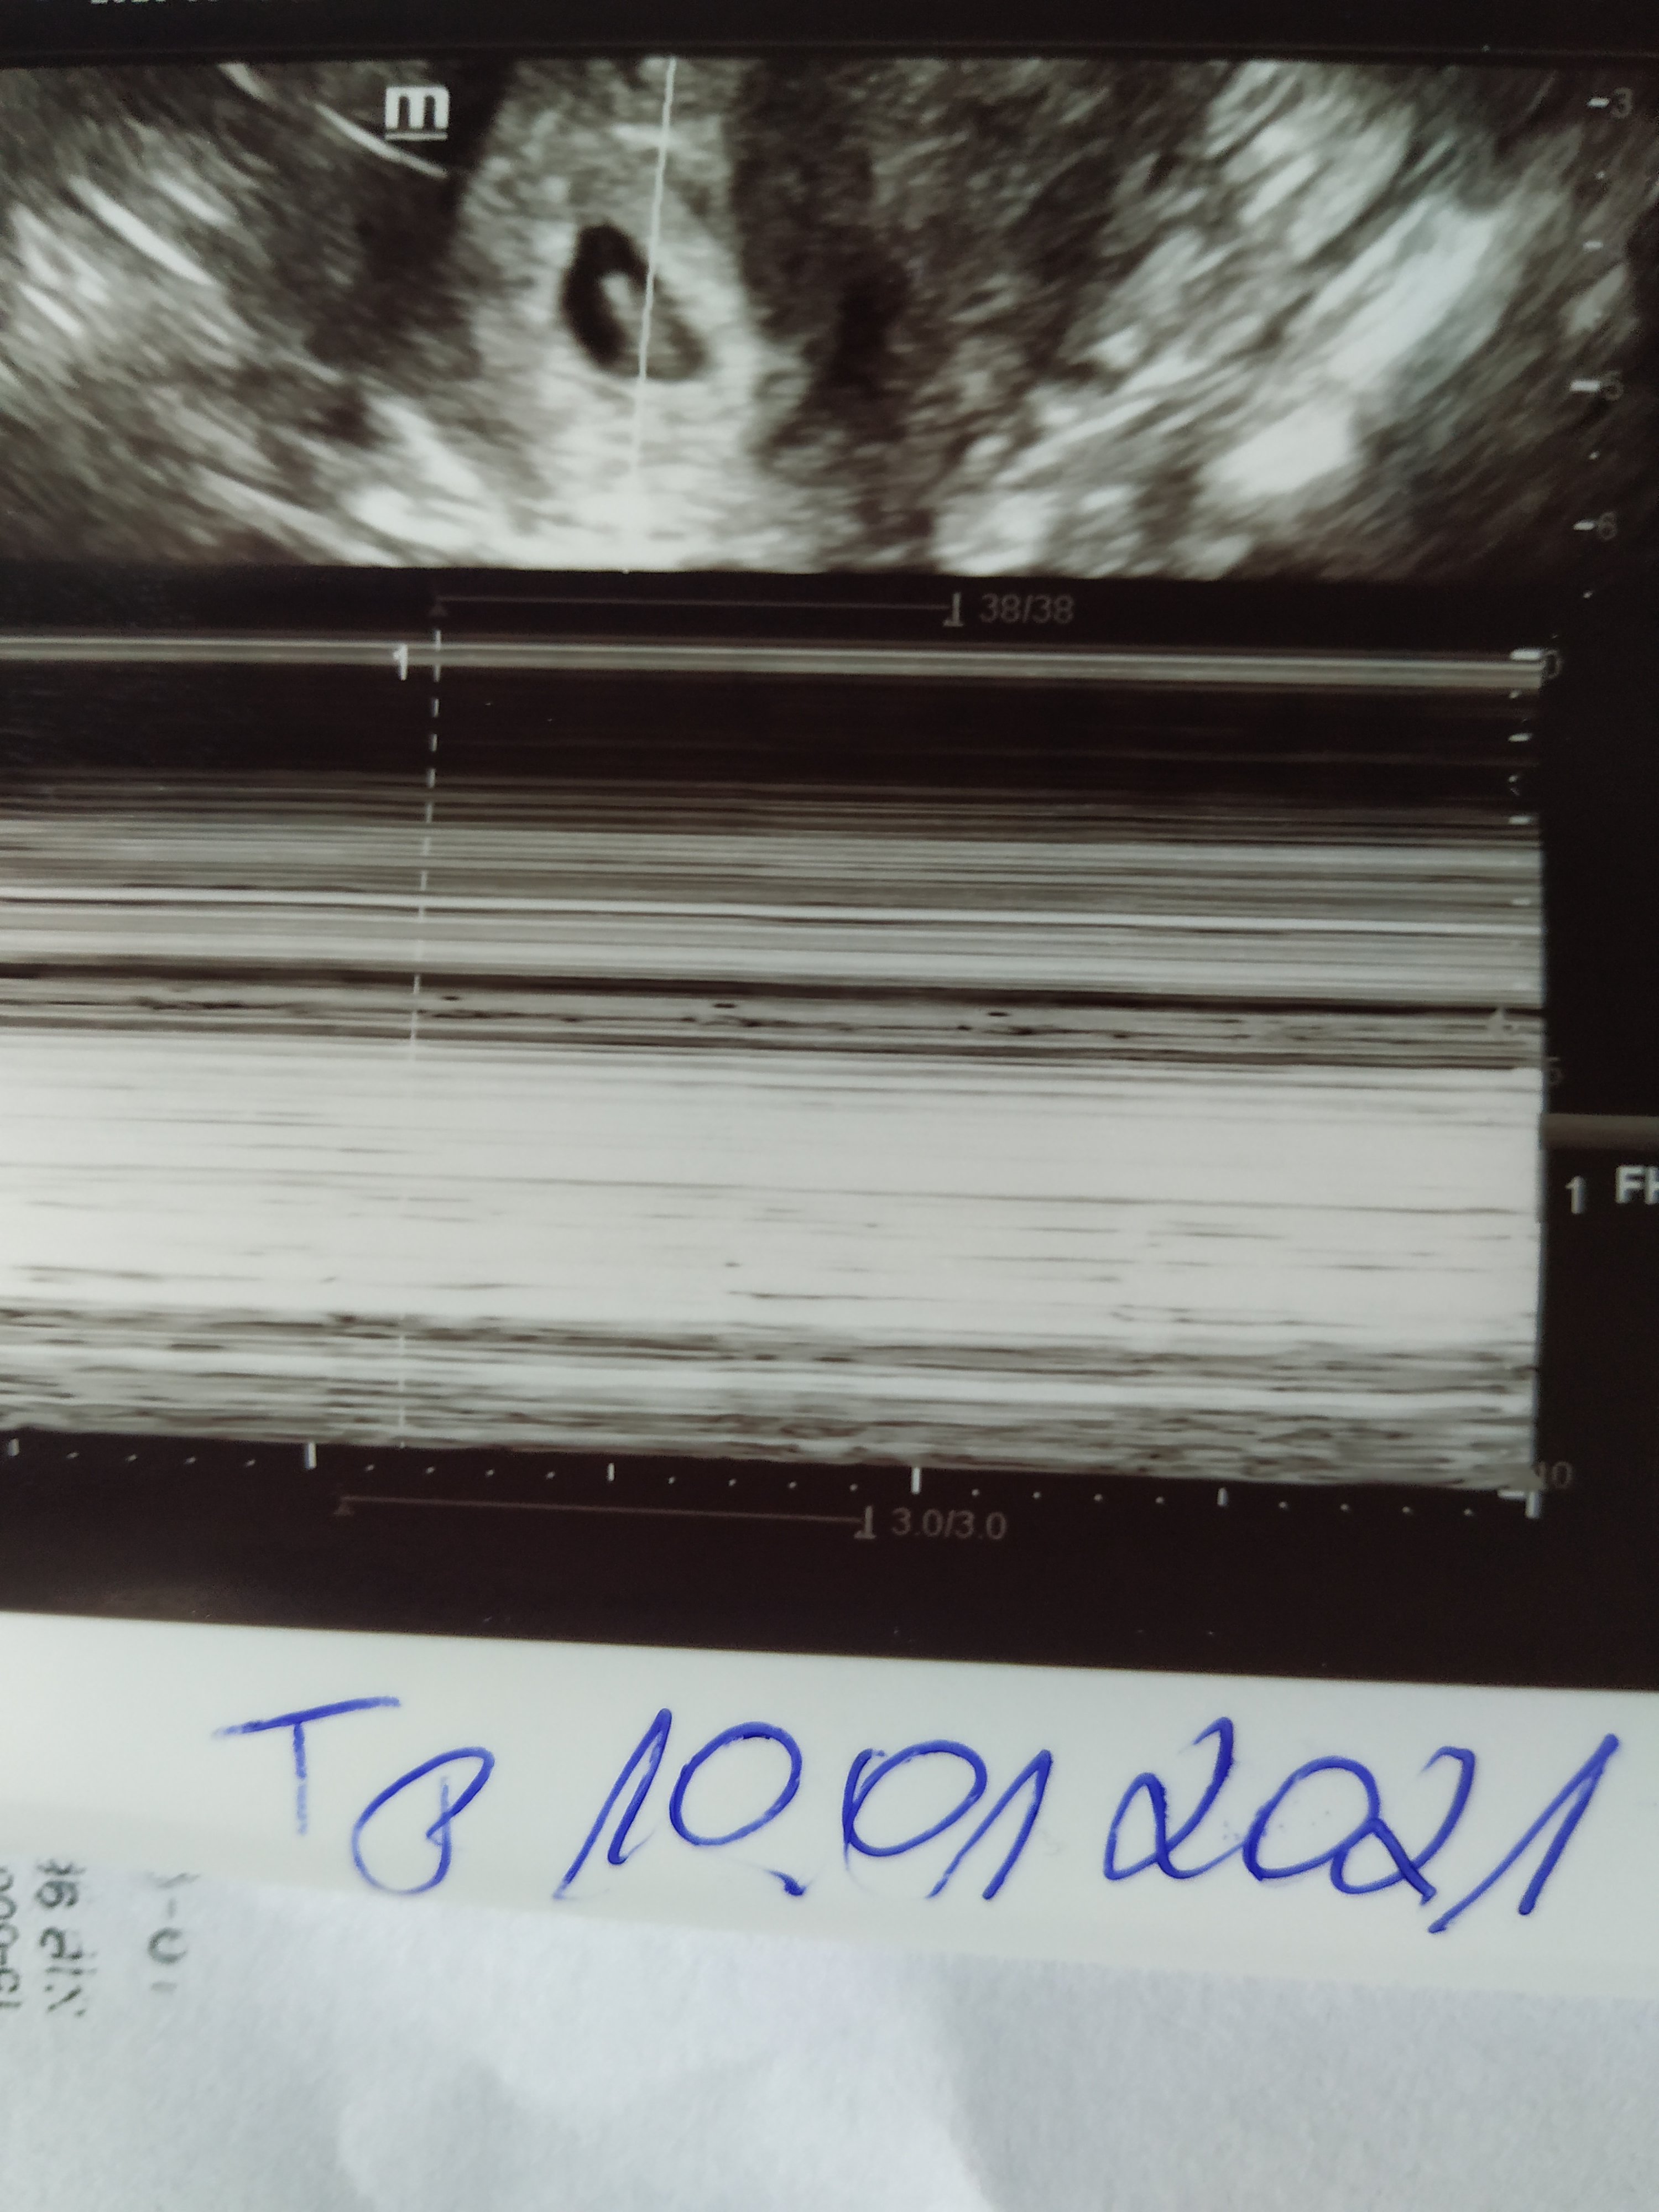

Ja takze mialam tylko plamke.. dzis ide jest u mnie 6+4 z apki